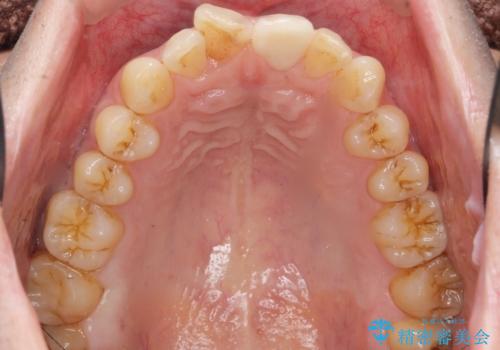

天然歯と見紛うほどの自然な仕上がりに喜んで頂けました。

クラウンの繊細なグラデーションや自然な表面性状・形態は熟練した技工士さんの技術の賜物です。

被せ物の種類:ジルコニアオールセラミッククラウン スペシャル